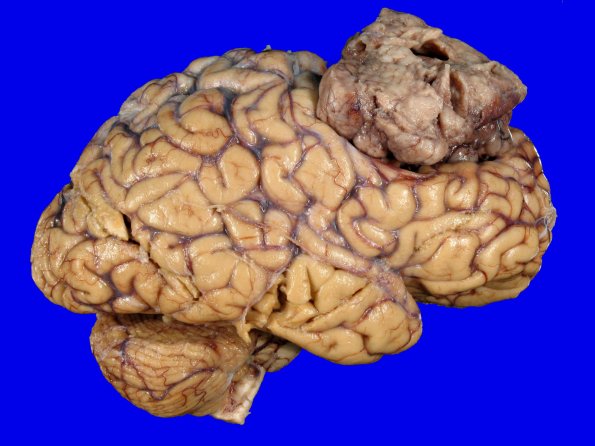

Washington University Experience | NEOPLASMS (MENINGIOMA) | Gross Pathology | 72C1 NCL (Case 72) Gross_6

72C1,2 The lateral view of the tumor and its relationship with the underlying brain which is deformed in response.